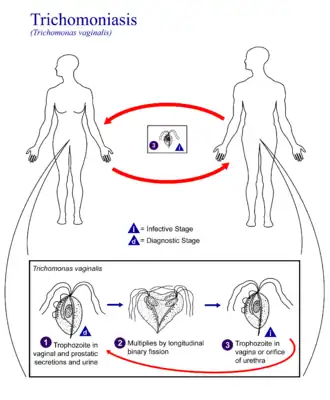

Жизненные циклы парабазалий чрезвычайно разнообразны. В качестве примера наиболее простого жизненного цикла можно привести таковой у паразита человека Trichomonas vaginalis, возбудителя венерического заболевания трихомониаз. Паразиты существуют только в виде пятижгутикового трофозоита, размножающегося бинарным делением. Передача от хозяина к хозяину происходит при половом контакте[11].

Самым распространенным паразитом человека среди парабазалий является вид Trichomonas vaginalis (влагалищная трихомонада), вызывающий венерическую болезнь — урогенитальный трихомониаз. По данным ВОЗ, ежегодно в мире регистрируются более 174 миллионов случаев заболевания этой инфекцией[23].